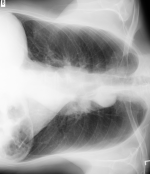

旋转

- 点击 变换 按钮左侧,或按 Ctrl + [,将图像逆时针旋转 90°

- 点击 变换 按钮右侧,或按 Ctrl + ],将图像顺时针旋转 90°